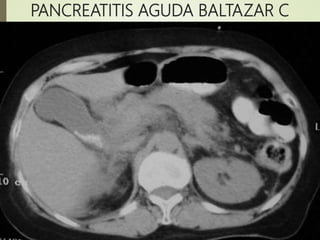

?? C 2 B+

<33% 2

PANCREATITIS AGUDA BALTAZAR C

TÉCNICAS DE IMAGEN oRadiografia simples(Descarta afecciones quirúrgicas abdominales) o Ecografia Abdominal(Para identificación de litiasis biliar) oTomógrafo Computadorizado(TC) o Criterios radiológico de gravedad de Balthazar El sistema desarrollado por Balthazar valora La extensión de la necrosis pancreática y presencia de lesiones extrapancreáticas en niveles de puntuación de 0-10, en que la puntuación 7-10 se asocia com mayor mortalidad 17% y morbilidad 92%

Panc. Grado PtsDescripción morfológica Necrosis Pts PAL A O Páncreas normal O% O PAL B 1 Aumento focal o difuso de páncreas O% O ?? C 2 B+ Inflamación Peri- Pancreática <33% 2 PAG D 3 C+ Colección líquida única 33-50% 4 PAG E 4 D+ dos colecciones líquidas y gás 50% 6